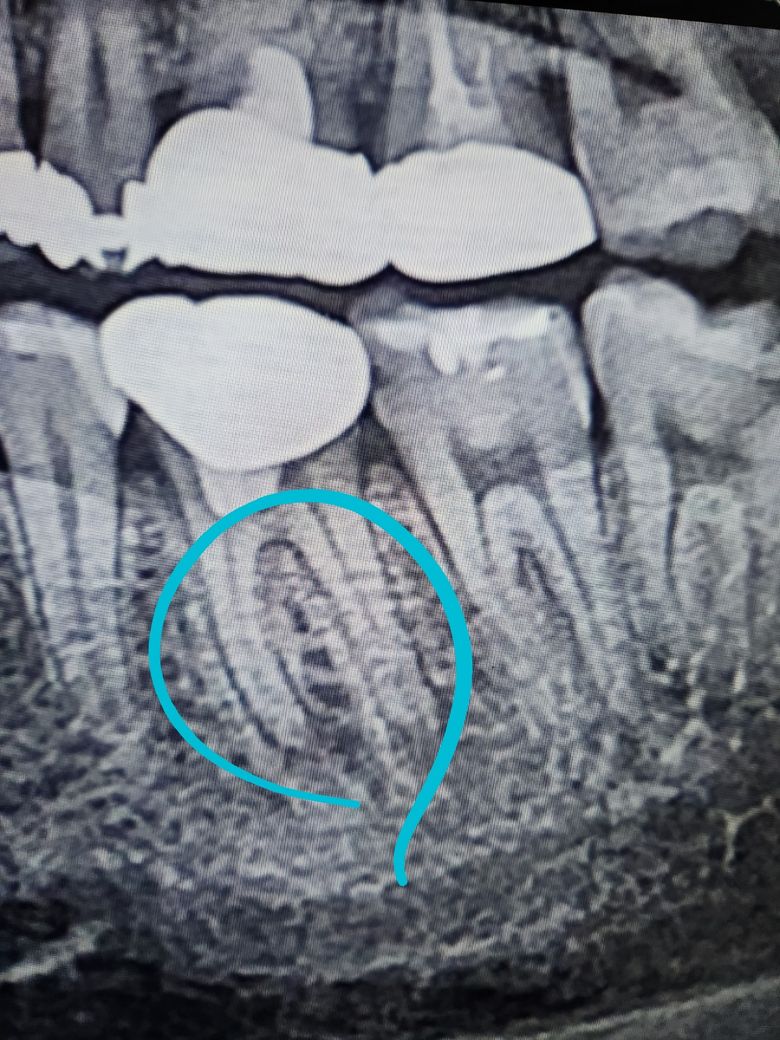

재신경치료해야해서 하늘색 동그라미 뿌리끝 염증인데 석회화로인해서 재신경치료 들어가야 합니다

사진 3장 각각 달마다 다른사진인데 염증이 커지는것같이 보이나요 아니면 다 비슷비슷하나요?

1. 사진 상으로는 염증이 커져보이는지에 대해서는 판단하기 어렵지만 염증의 경계가 불규칙한 것으로 보아 진행성으로 보여집니다. 치료를 하셔야 할 것으로 보입니다.

2. 일단 말씀하신 것 중에서 재신경치료라고 하지만 현재 2치아 모두 신경치료의 흔적은 없습니다. 신경치료 없이 크라운 및 치료를 한 것으로 보입니다. 따라서 재신경치료가 아닌 신경치료라고 보셔야 합니다.

-염증의 크기는 차이가 없어 보입니다.